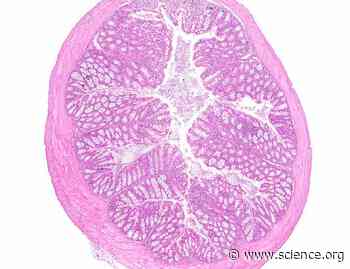

The E3 ligase TRIM13 restrains LPS-induced inflammation by reducing STIM1 abundance and the IRE1α-dependent unfolded protein response | Science Signaling